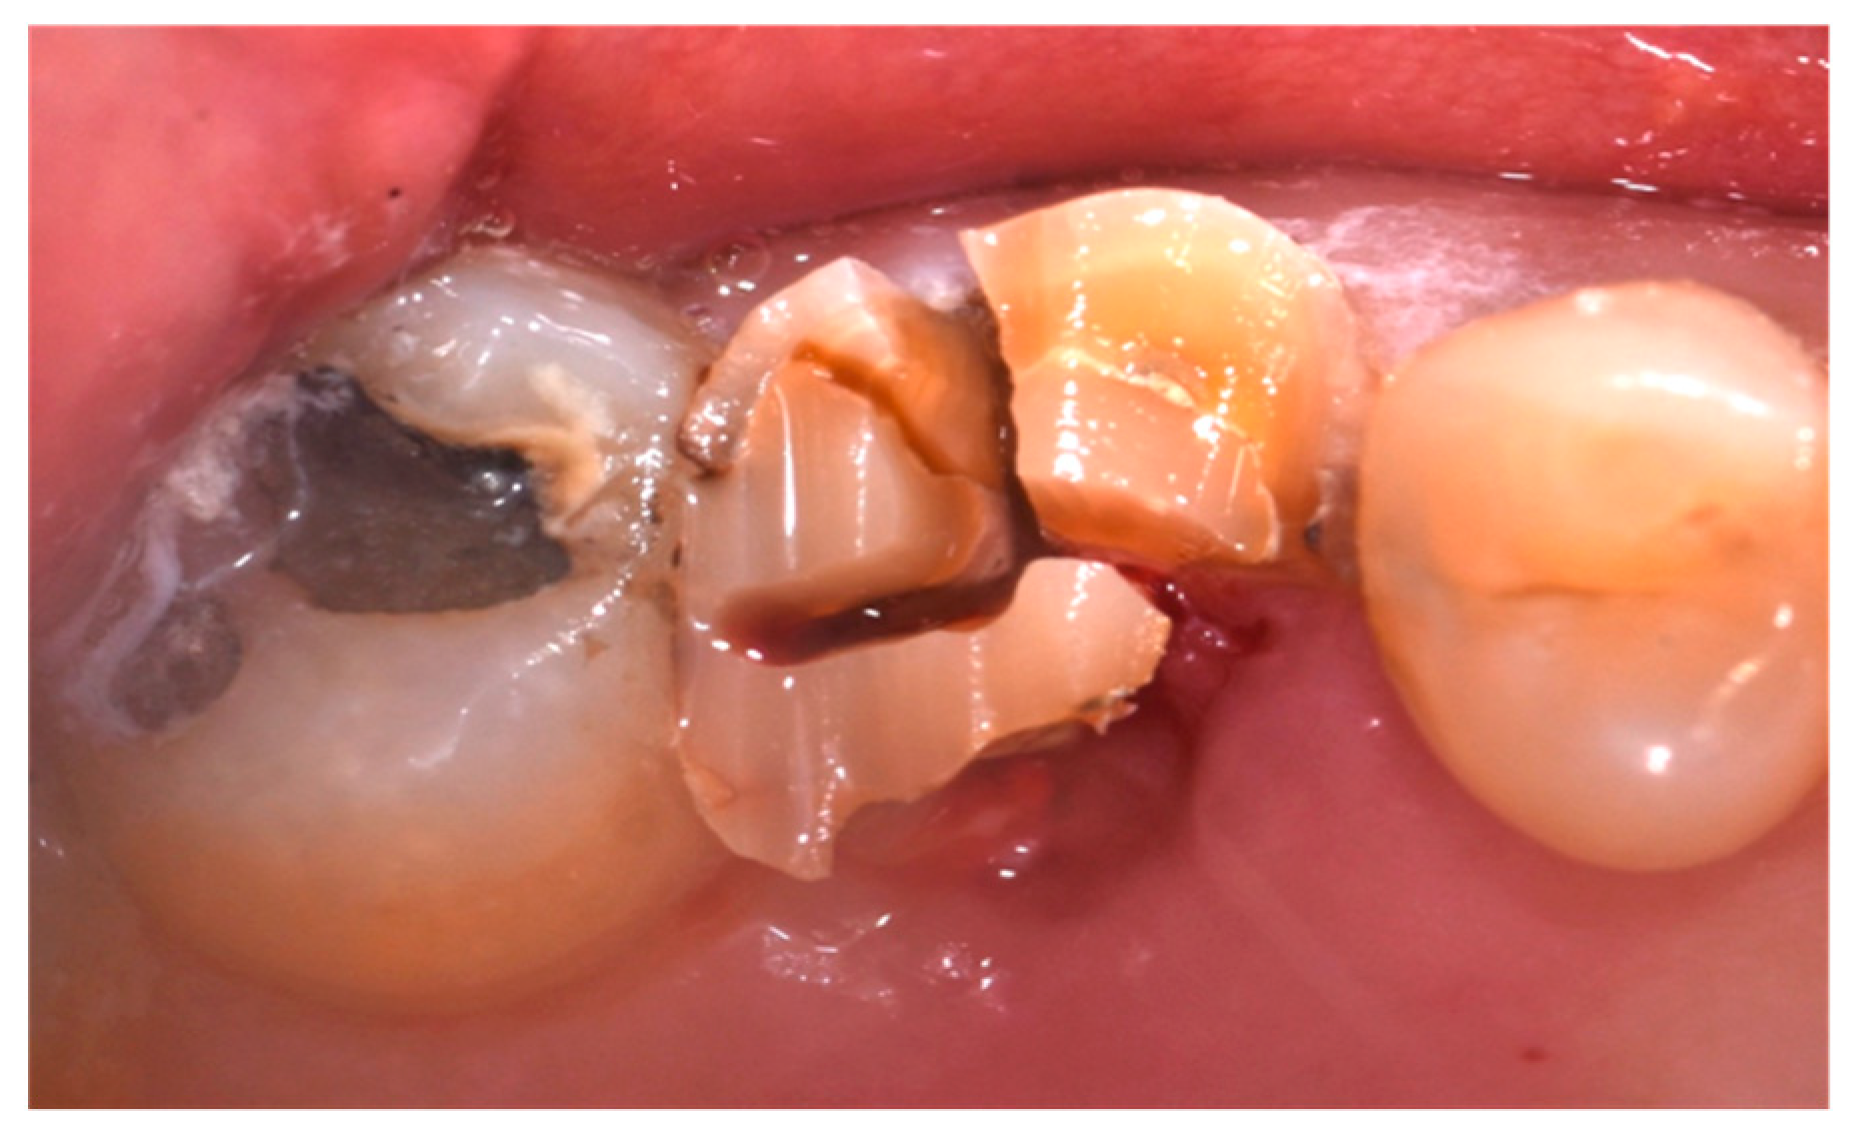

- Presence of at least one severely compromised dental element to be extracted;

- Cause of extraction: caries, orthodontic reasons, or trauma;